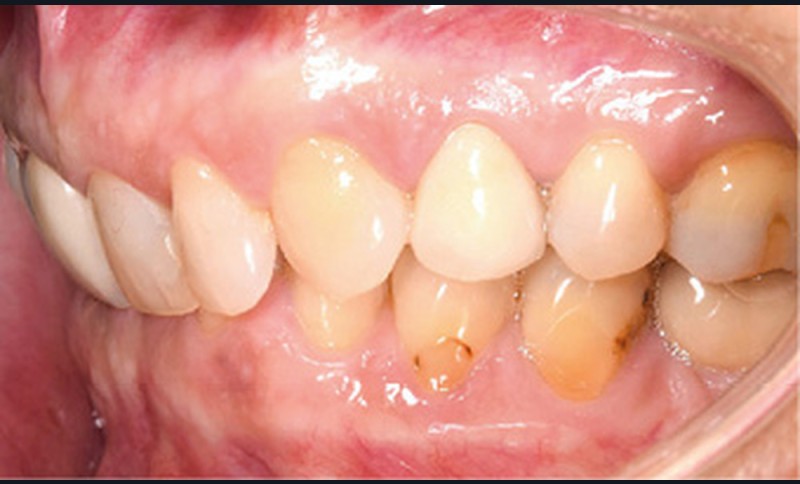

Examen endobuccal (fig. 2a-e)

L’arcade maxillaire est asymétrique et parabolique. Elle présente une mésio-position du secteur 1. On note des rotations mésio-vestibulaire de 13 et disto-vestibulaire de 23 et une palato-version incisive. Les restaurations prothétiques sur 11, 16 et 24 semblent à refaire. L’arcade mandibulaire est asymétrique et parabolique avec une couronne sur implant en 36.

Dans la dimension transversale, on constate une endoalvéolie maxillaire. Dans la dimension sagittale, on observe une classe II plus importante à droite où elle est complète de 5 mm. Le surplomb est absent et la supraclusion totale (6 mm) par supra-alvéolie mandibulaire.